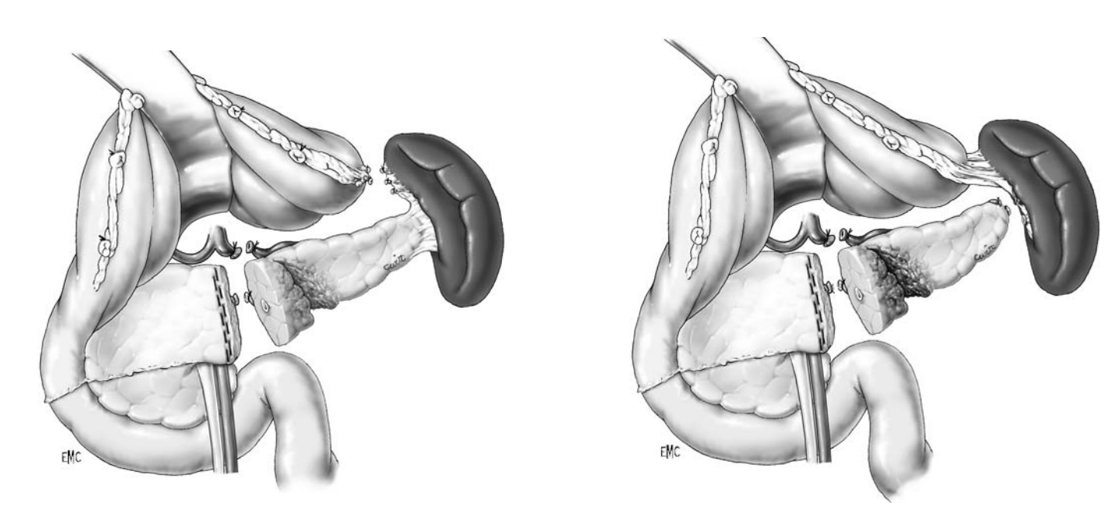

Trường hợp máu đã ngừng chảy thì chỉ cần lấy máu cục quanh gan, rửa sạch ổ bụng, đặt dẫn lưu (nếu cần). Trường hợp chảy máu nhiều từ gan có thể cầm máu tạm thời bằng cách ép gan bằng tay (Hình 2), ép gan với hai tay và ép vào cơ hoành, giao cho người phụ giữ, kiểm soát cuống gan toàn bộ (thủ thuật Pringle) (Hình 3), nhanh chóng thăm dò ổ bụng để loại trừ các nguồn chảy máu khác.

Hình 2. Kỹ thuật dùng tay ép nhu mô gan cầm máu tạm thời

Hình 3. Thủ thuật Pringle và Kiểm soát toàn bộ mạch máu gan